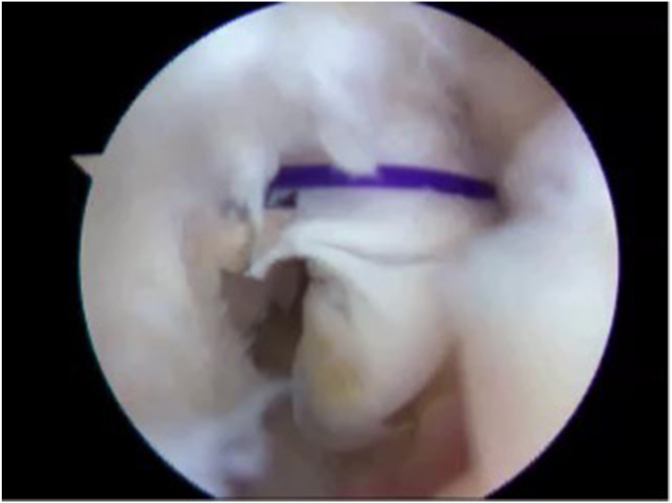

Fig. 6.

Repair of a lateral capitellar fracture utilizing an absorbable suture anchor and substituting the normal suture with an absorbable suture, a modification of the Michael Hausman technique for repair.